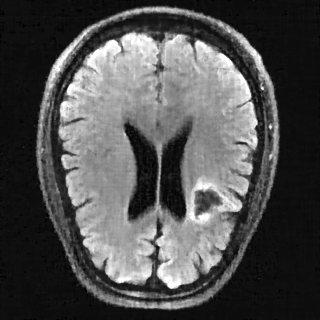

This article presents a novel undersampled magnetic resonance imaging (MRI) technique that leverages the concept of Neural Radiance Field (NeRF). With radial undersampling, the corresponding imaging problem can be reformulated into an image modeling task from sparse-view rendered data; therefore, a high dimensional MR image is obtainable from undersampled $k$-space data by taking advantage of implicit neural representation. A multi-layer perceptron, which is designed to output an image intensity from a spatial coordinate, learns the MR physics-driven rendering relation between given measurement data and desired image. Effective undersampling strategies for high-quality neural representation are investigated. The proposed method serves two benefits: (i) The learning is based fully on single undersampled $k$-space data, not a bunch of measured data and target image sets. It can be used potentially for diagnostic MR imaging, such as fetal MRI, where data acquisition is relatively rare or limited against diversity of clinical images while undersampled reconstruction is highly demanded. (ii) A reconstructed MR image is a scan-specific representation highly adaptive to the given $k$-space measurement. Numerous experiments validate the feasibility and capability of the proposed approach.